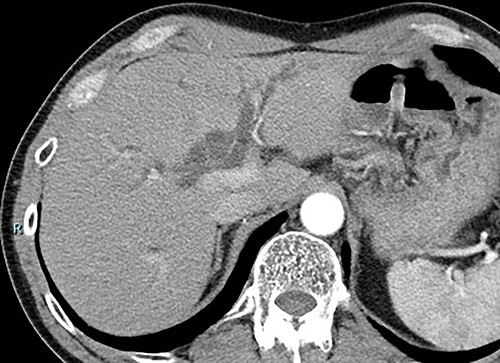

Contrast-enhanced computed tomography (CT) revealed wall thickening and stricture of the distal common bile duct (CBD) (Fig. 1). Dilation of both the intrahepatic bile ducts and the common hepatic duct was also observed (Fig. 2). No lymph node or distant metastases were observed. Endoscopic retrograde cholangiopancreatography revealed irregular stenosis in the distal CBD (Fig. 3). Thereafter, biliary drainage and brush cytology were performed, and an adenocarcinoma was detected.

Macroscopically, there was a gray invasive nodular tumor measuring 19 × 18 × 15 mm at the distal CBD (Fig. 4). Histopathological examination showed that the tumor comprised two components; well-differentiated adenocarcinoma of the CBD mucosa (20%) and proliferation of small atypical cells forming follicular nests with invasion around the CBD wall (80%) (Fig. 5a and b). The invasion extended to the pancreas and duodenal muscular layer. Immunohistochemical examination revealed that the solid proliferative lesions of small atypical cells were positive for chromogranin A and synaptophysin (Fig. 6a–c). The Ki-67 index was ~80% (Fig. 6d). No lymph node metastasis was detected. The patient was finally diagnosed with small-cell NEC (pT2N0M0, pStage I B) of the EHBD. R0 resection was achieved pathologically and there was no recurrence for 4 months after surgery.